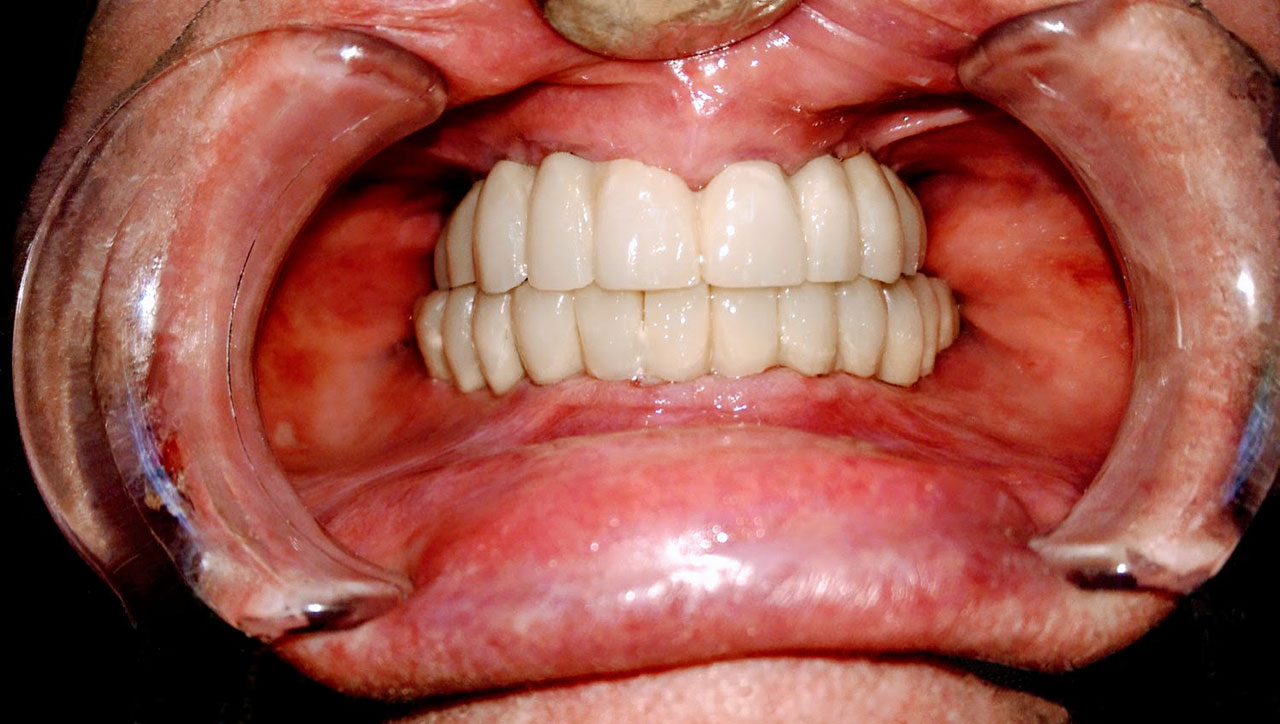

72 órával az alsó-felső állcsont teljes implantációs helyreállítása után, így mosolyog a páciens a beragasztott, fix hidakkal.

• esettanulmany-15

• esettanulmany-32

72 órávan a felső állcsont teljes implantációs helyreállítása után, így mosolyog a páciens a beragasztott, fix hiddal.